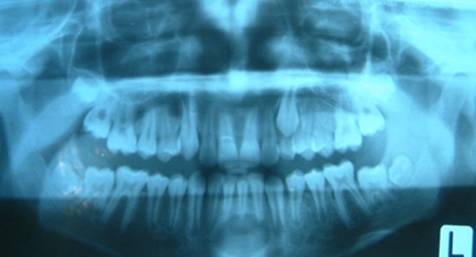

Fig.38 Ortopantomografia unui pacient ce prezinta o radiotransparenta in zona mediana mandibulara, corespunzatoare unui "chist median mandibular".

Chistul median mandibular reprezinta expresia clinica a unui chist radicular cu punct de plecare la nivelul incisivilor inferiori, cu toate caracterele clinice, radiografice, histopatologice, de evolutie si tratament ale acestuia.